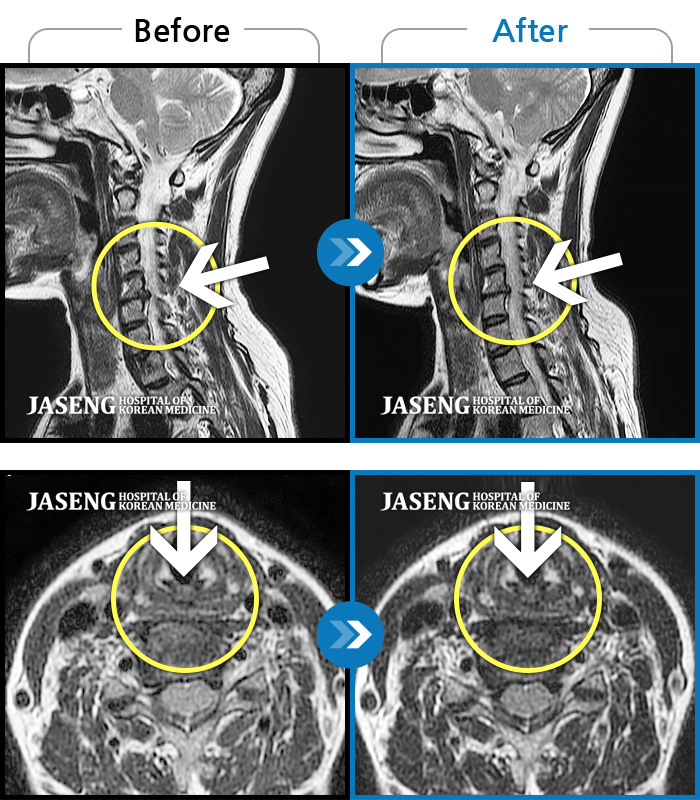

목디스크

도움받은 사례

인천 · 강아현 원장

처음 내원시 목에서 등으로 이어지는 통증 및 우측 팔 저림 증상이 심했고, 약간의 근력저하도 동반되어 일상생활이 어려운 상태였습니다.

촬영시기

2024.04.06 ~ 2024.11.16

2024.11.22

조회수 17,047